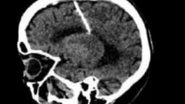

Idosa viveu a maior parte de sua vida com a agulha enfiada no cérebro